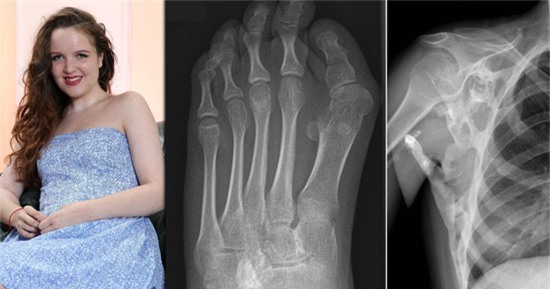

(DNVN)-Một chứng bệnh hiếm gặp về gene đang dần dần làm tê liệt toàn bộ cơ thể của một thiếu nữ xinh đẹp người Anh và có thể chứng bệnh này sẽ biến cô thành một "pho tượng sống".